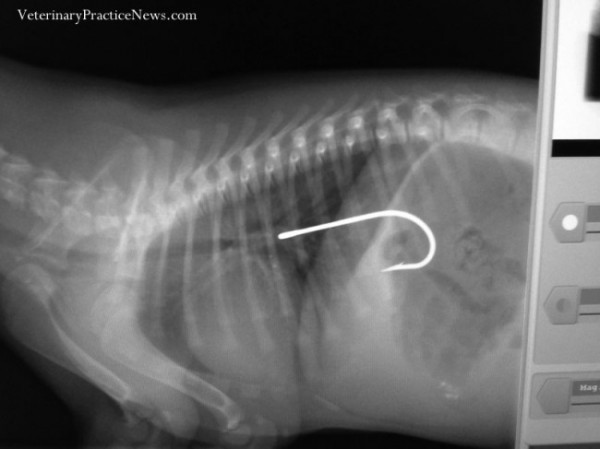

Рыбацкий крючок